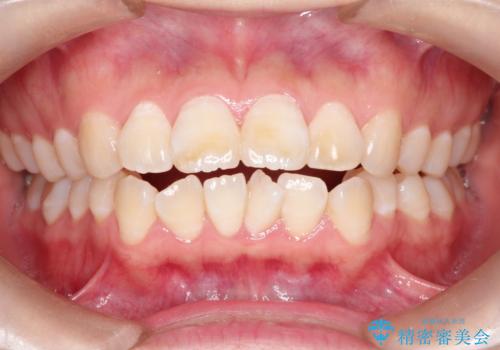

- ”口元を下げたい”が主訴で来院されました。

抜歯してワイヤー矯正を行い、口元も改善され大変満足していただきました。